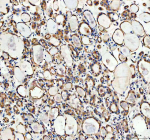

Immunohistochemical staining of CYP26B1 using anti-CYP26B1 antibody. CYP26B1 was detected in a paraffin-embedded section of human liver cancer tissue. Heat mediated antigen retrieval was performed in EDTA buffer (pH 8.0, epitope retrieval solution). The tissue section was blocked with 10% goat serum. The tissue section was then incubated with 2 ug/ml rabbit anti-CYP26B1 antibody overnight at 4oC. Peroxidase Conjugated Goat Anti-rabbit IgG was used as secondary antibody and incubated for 30 minutes at 37oC. The tissue section was developed using an HRP secondary and DAB substrate.